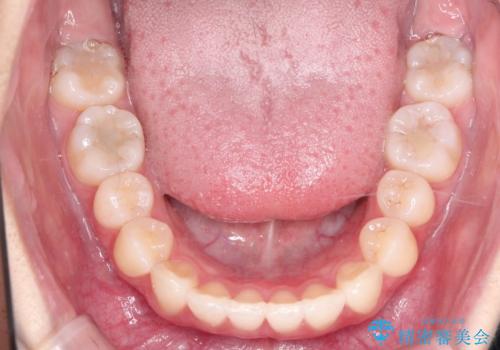

前歯のがたがたを綺麗にしたい

- 前歯がねじれていること、出ていることを主訴に来院されました。

前歯の突出感も改善され、満足していただきました。